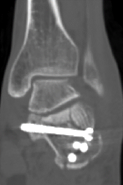

术后影像显示螺钉位置良好